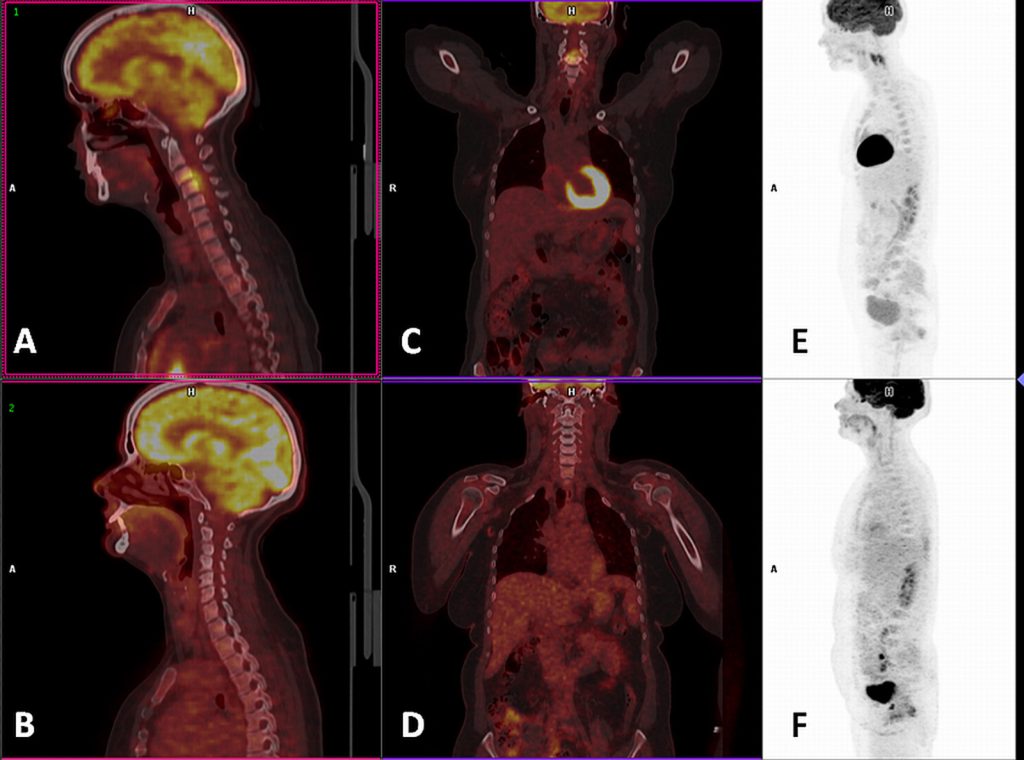

F-FDG PET–CT